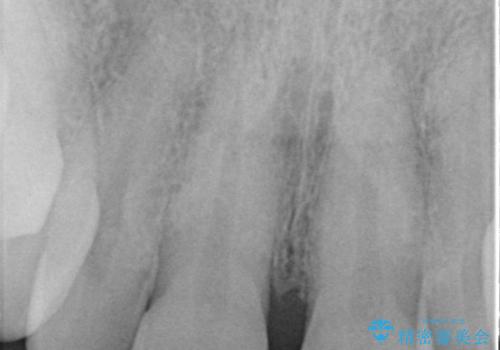

- 前歯のすきっ歯を気にして来院された患者様です。

矯正かオールセラミックか、治療の選択がありましたが、ご年齢や色の濃い点を考慮してオールセラミッククラウンにて補綴することとしました。

折角なのできれいに仕上げたいとのことで、オーダーメイドタイプのクラウンを選択されました。色調を周りのご自身の歯と合わせることができるため、自然な仕上がりをご希望の方におすすめです。